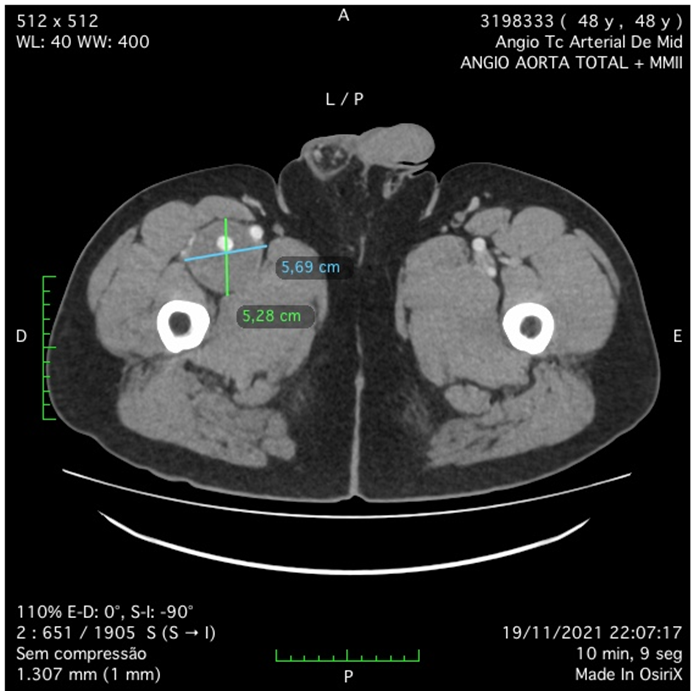

A 49 year-old male patient, with no comorbidities, except for occasional smoking and overweight, was admitted with right limb pain, mainly in the thigh, associated with a weakness and difficulty to walk in the past seven days. The patient was submitted to a duplex ultrasound, that suggested a dilatated deep femoral artery, with 6 cm diameter. On physical examination, he had a good general health, with a pulsating bulge with fibroelastic consistency palpable in the right inguinal region. The patient had femoral, popliteal and distal pulses present bilaterally. The patient was submitted to a duplex ultrasound, that suggested a deep femoral artery aneurysm, with 6 cm diameter. and then. The patient was submitted to a computed tomography angiography (CTA) of the abdomen, pelvis and inferior limbs bilaterally. The CTA showed no other abnormalities in the arterial system, except for an isolated right deep femoral artery aneurysm, with 6,6 cm diameter. (Figures 1 and 2). The distance between the origin of the deep femoral artery aneurysm and the femoral common bifurcation was satisfactory (36,685cm), providing an adequate neck length for endovascular treatment (Figures 2-4). The proximal landing zone had 7,8mm diameter and distal landing zone had 7mm diameter. The total length of the DFAA was 6,85cm. Since there is no consensus in the literature regarding the best way to treat those kind of aneurysms, both techniques, open surgery and endovascular treatment, were extensively explained to the patient. The surgical team and the patient had decided to perform endovascular treatment.

Figure 1: Angio-CT scan in axial incidence showing deep femoral artery aneurysm (DFFA).